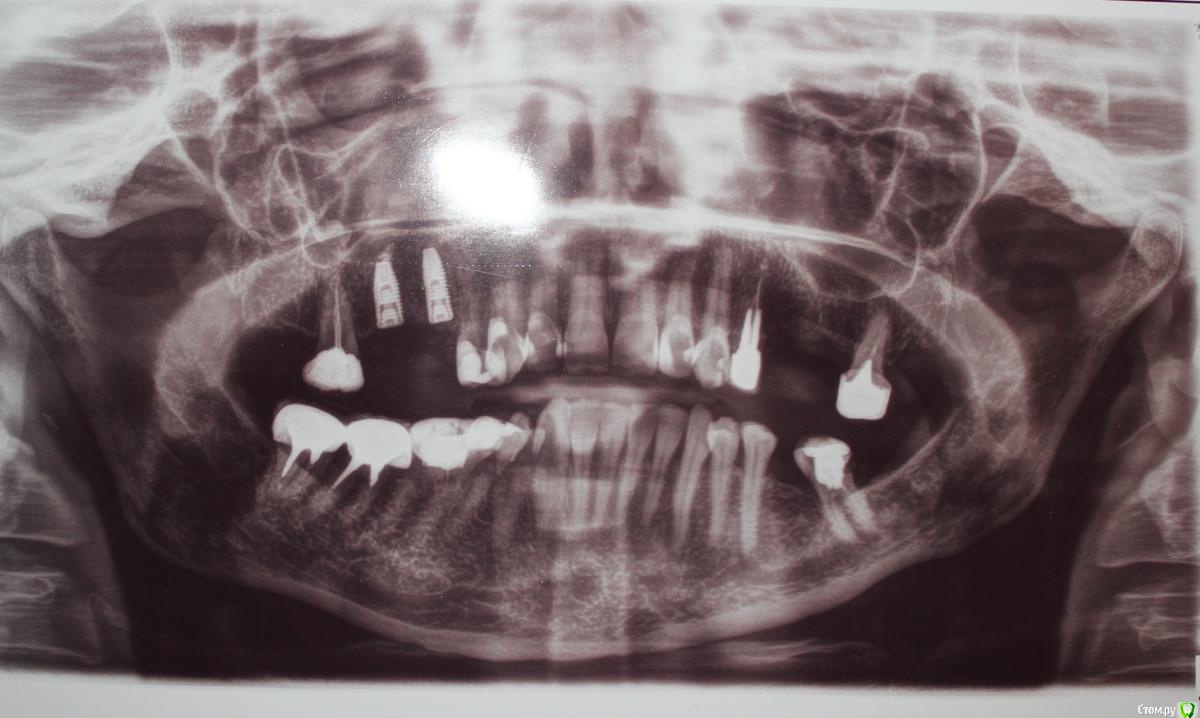

Patient_Nobel Опубликовано 27 июля, 2019 Поделиться Опубликовано 27 июля, 2019 (изменено) Здравствуйте, уважаемые форумчане! Поставили импланты , рядом с ними остался один зуб. Если по снимку смотреть - верхний левый крайний. Семерка ( по современному не знаю названия).До установки имплантов врач ничего о нём не говорил. А после установки сказал, что им нужно заниматься до установки коронок на импланты и для этого лучше посмотреть под микроскопом, в чем там проблема. Хотя они же мне делали КТ. Разве в разрезах КТ не видно всех проблем?Возможно, нужно будет ставить на него коронку.Что посоветуете? Действительно ли там что-то серьёзно нужно делать? Сейчас он меня совершенно не беспокоит. Изменено 27 июля, 2019 пользователем Patient_Nobel Ссылка на комментарий

St. Опубликовано 27 июля, 2019 Поделиться Опубликовано 27 июля, 2019 Добрый день. Да, все логично. На зубе сейчас масивная пломба, чтобы хорошо восстановить форму зубов на имплантах и плотность контакта между зубами и новыми коронками логично покрыть 7 зуб коронкой. Перед этим проверяют как лечены каналы (насколько плотно и т.д.) под микроскопом это делать удобнее, и по необходимости перелечивают. Ссылка на комментарий

red_butler Опубликовано 31 июля, 2019 Поделиться Опубликовано 31 июля, 2019 И ещё мне не понятно - этот зуб обязательно нужно лечить? для отвела нужна Кт Там какие-то проблемы сейчас видны? большая степень разрушения Ссылка на комментарий